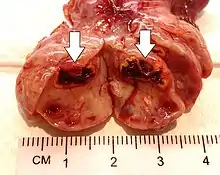

Gross pathology of a corpus luteum cyst with bleeding

This type of functional cyst occurs after an egg has been released from a follicle. The follicle then becomes a secretory gland that is known as the corpus luteum. The ruptured follicle begins producing large quantities of estrogen and progesterone in preparation for conception. If a pregnancy doesn't occur, the corpus luteum usually breaks down and disappears. It may, however, fill with fluid or blood, causing the corpus luteum to expand into a cyst, and stay in the ovary. Usually, this cyst is on only one side, and does not produce any symptoms.[1][2]